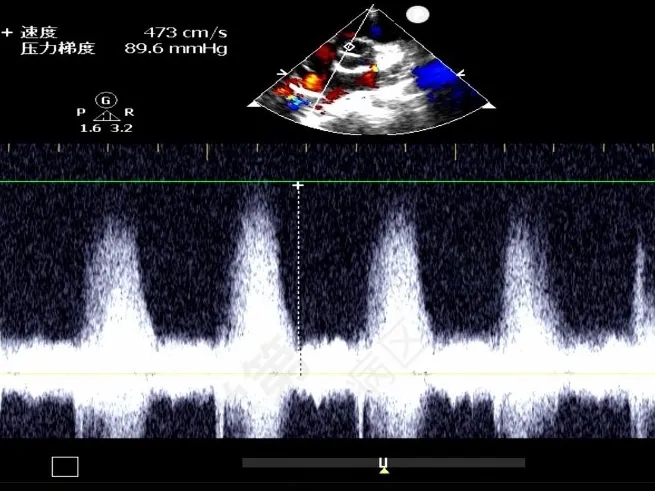

门诊心脏彩超提示:

超声多切面示:室间隔膜周部可见连续中断,局部不规则向右室膨出,呈“囊袋状”,断端回声增强,测缺口大小:左室面6.5mm、右室面2.5mm,隔瓣下残缘5mm,彩色血流示:室水平左向右分流,Vmax 473cm/s,Pgmax 89 mmHg。